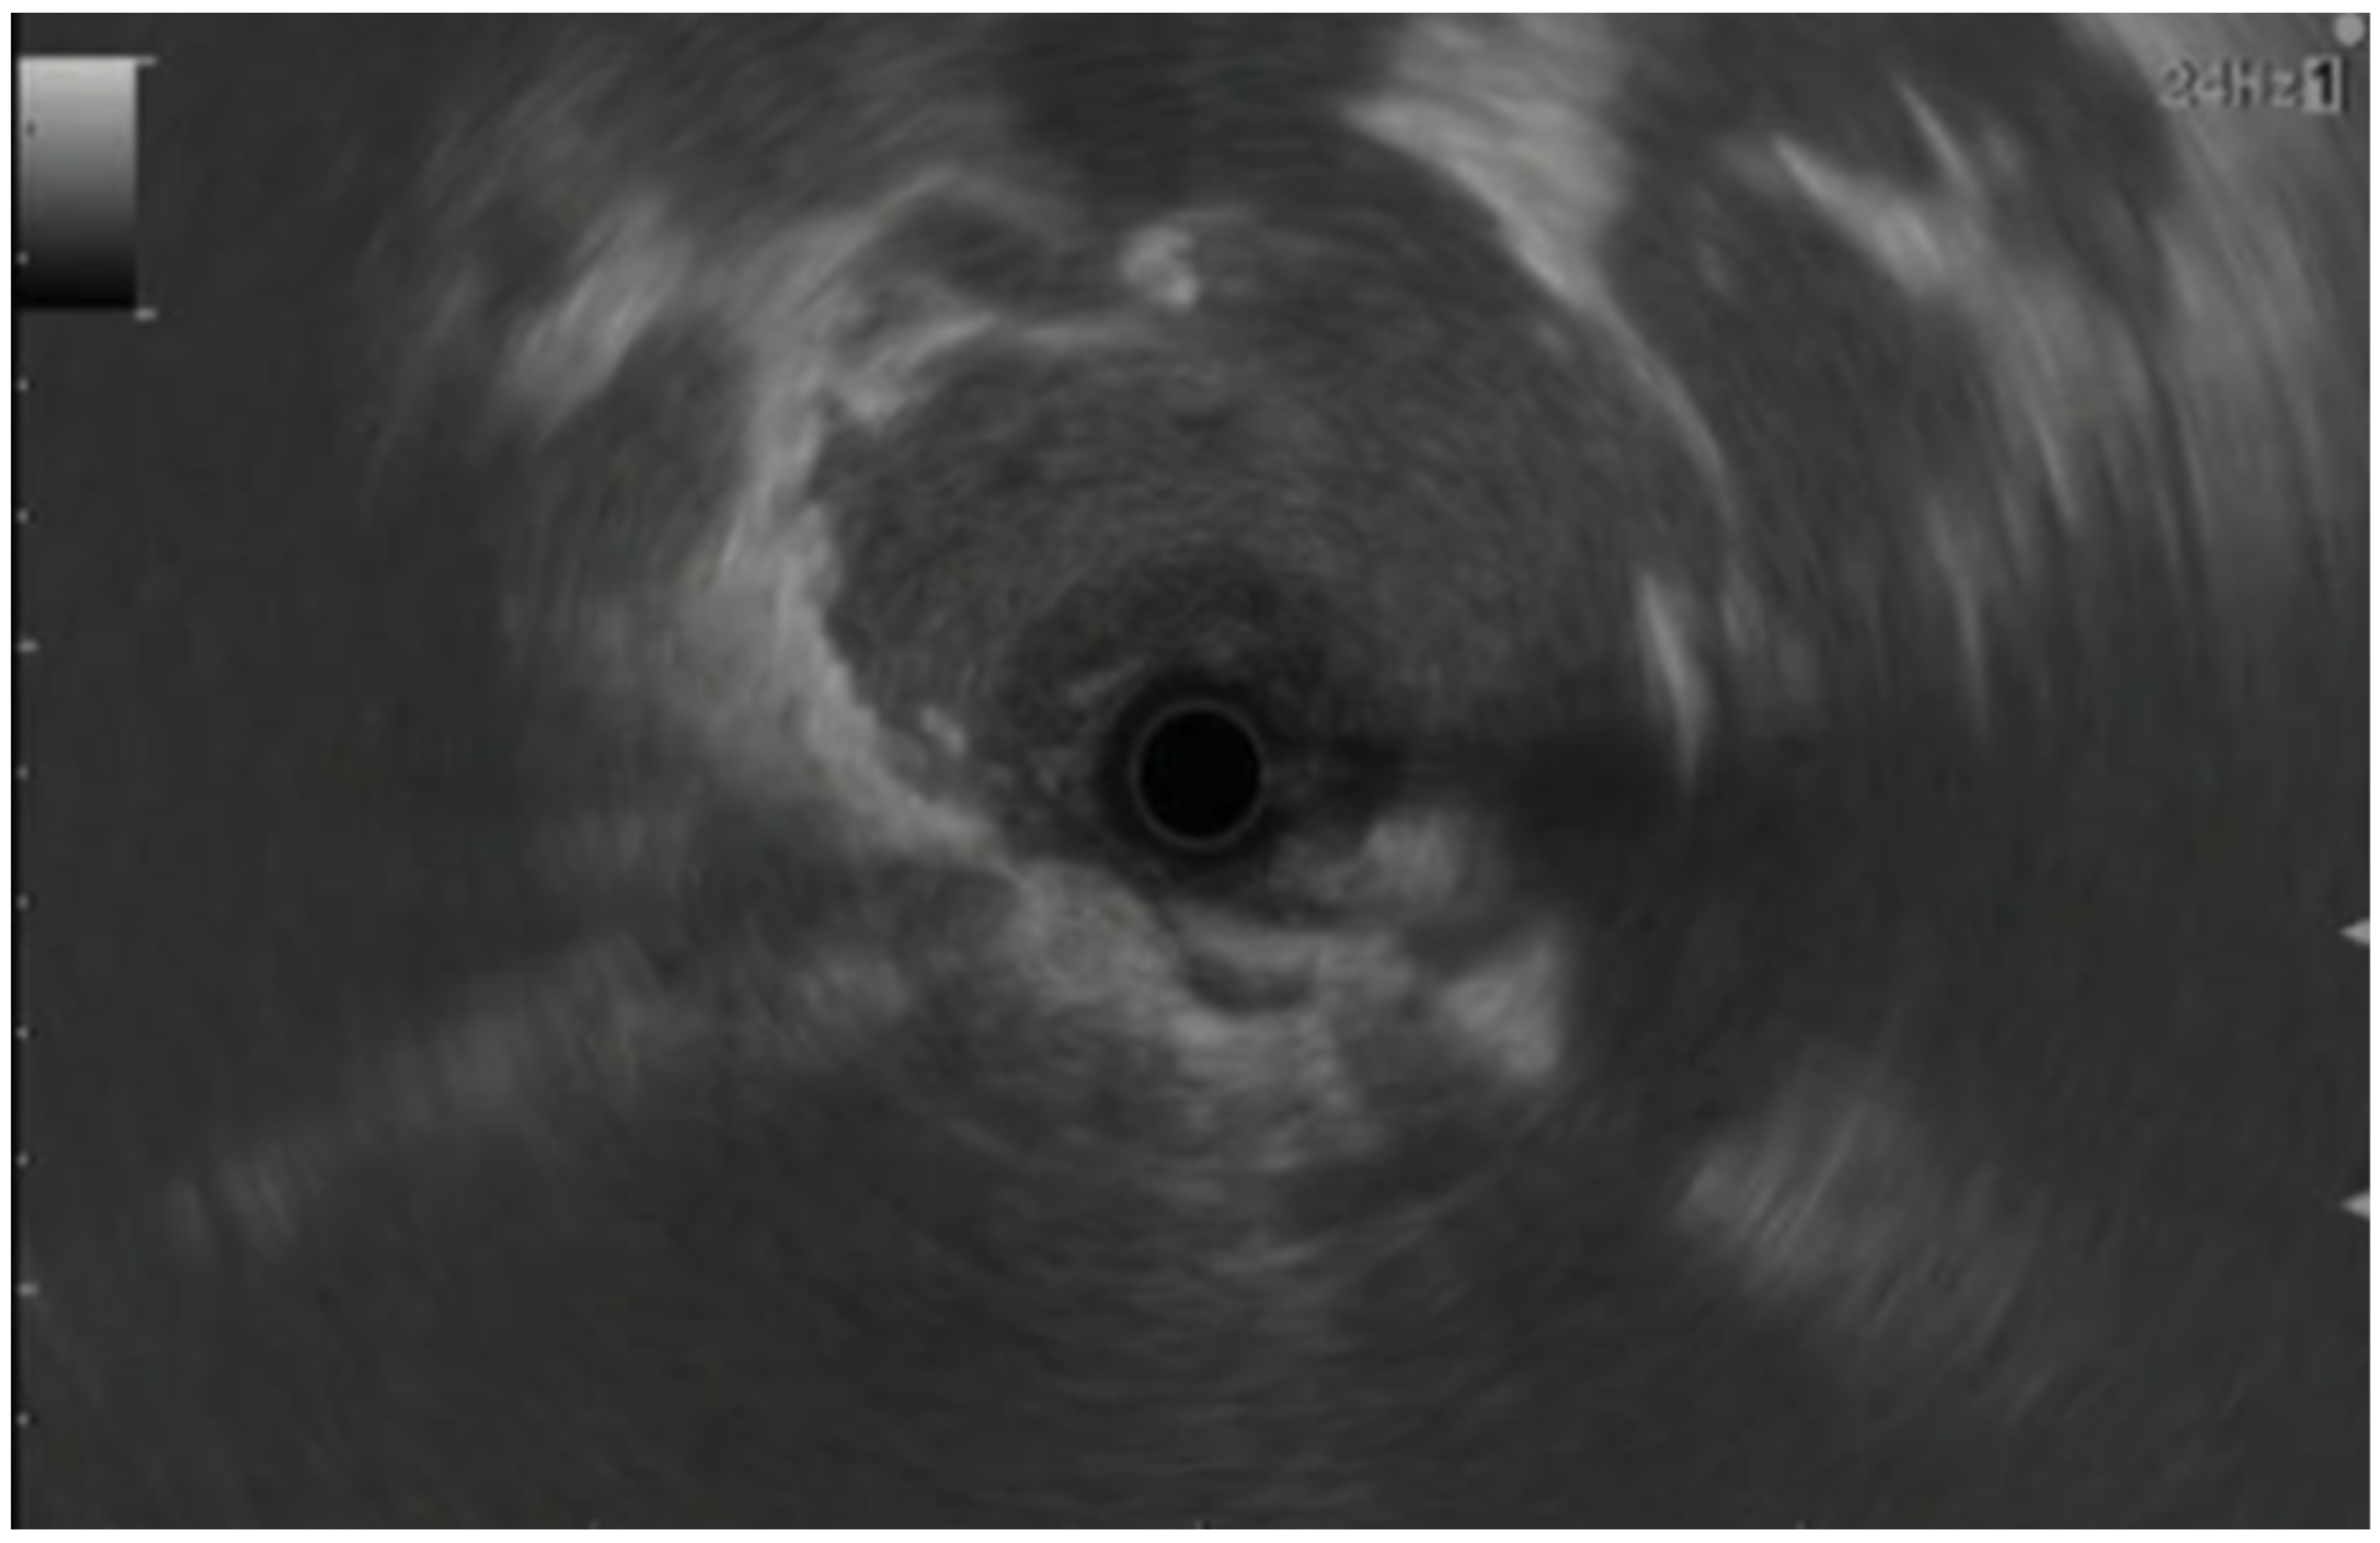

3. Conventional (Radial and Linear) Endoscopic Ultrasound